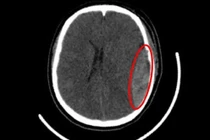

Nam sinh lớp 10 đang đi bộ về nhà thì bị nhóm thanh thiếu niên mang gậy tấn công dã man, gục tại chỗ. Nạn nhân bị nứt sọ, tụ máu bầm, hiện đang được cấp cứu.

Bệnh nhân nhập viện trong tình trạng nguy kịch, ổ dập não, tụ máu dưới màng cứng và vỡ xương sọ... Sau 5 ngày phẫu thuật, hồi sức tích cực... bệnh nhân đã hồi phục thần kỳ.